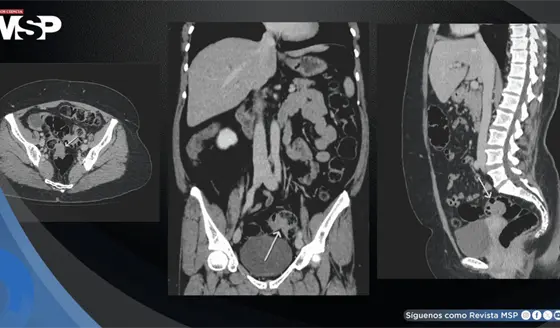

Endometriosis intestinal infiltrativa simuló cáncer colorrectal al producir sangrado rectal y estenosis